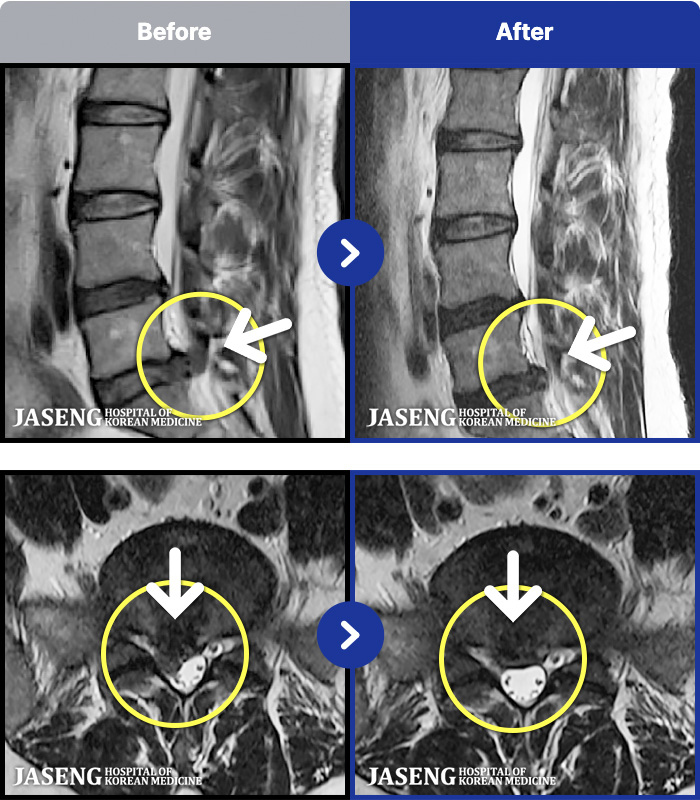

ȯںп Ǹ ǿ ԿǾ, ο ġ ۿ Ƿ ġḦ Ͻñ ٶϴ.